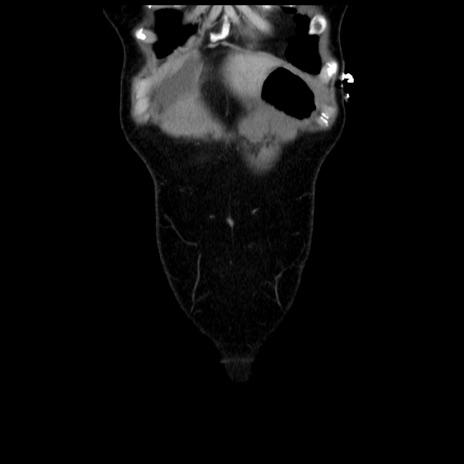

症例10(冠状断像)

【症例】 50歳代女性

【主訴】 腹痛

【現病歴】前日生レバーを食べた。今朝に排便あり。 昼前に突然発症の腹痛を生じ、当院救急外来を受診した。

【既往歴】 子宮筋腫にてで子宮全摘後

【身体所見】 意識清明、腹部:平坦、軟、下腹部やや左を中心に圧痛・反跳痛あり、筋性防御あり

【データ】WBC 7800、CRP 0.07